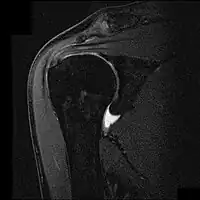

![]() Imagen por resonancia magnética nuclear mostrando el pinzamiento y ruptura parcial del tendón del músculo supraespinoso. | ||

En el caso de complementar con pruebas imagen, a menudo se utiliza la radiografía, el examen por ultrasonido y la resonancia magnética nuclear para confirmar la sospecha diagnóstica. La radiografía permite descartar que existan espolones o anomalías en la morfología del acromion que se hayan constituido como causa del síndrome, así como otras patologías identificables a través de esta prueba de imagen como la tendinitis calcificante, fracturas o neoplasias. El ultrasonido es una forma rápida, precisa y barata de evaluar posibles roturas parciales del manguito.[13] Sin embargo, dentro de las pruebas radiológicas, la resonancia magnética nuclear se considera el gold standard para evaluar roturas parciales o totales de los tendones afectados, aunque un estudio halló que esta solo se realiza en el 5,2% de los sujetos afectados.[14]